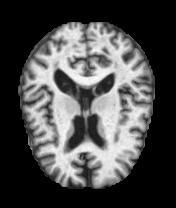

MRI Brain Scans Dataset - All Categories

Normal Cognition

Healthy brain structure

Real MRI scans showing progressive structural brain changes across all dementia stages